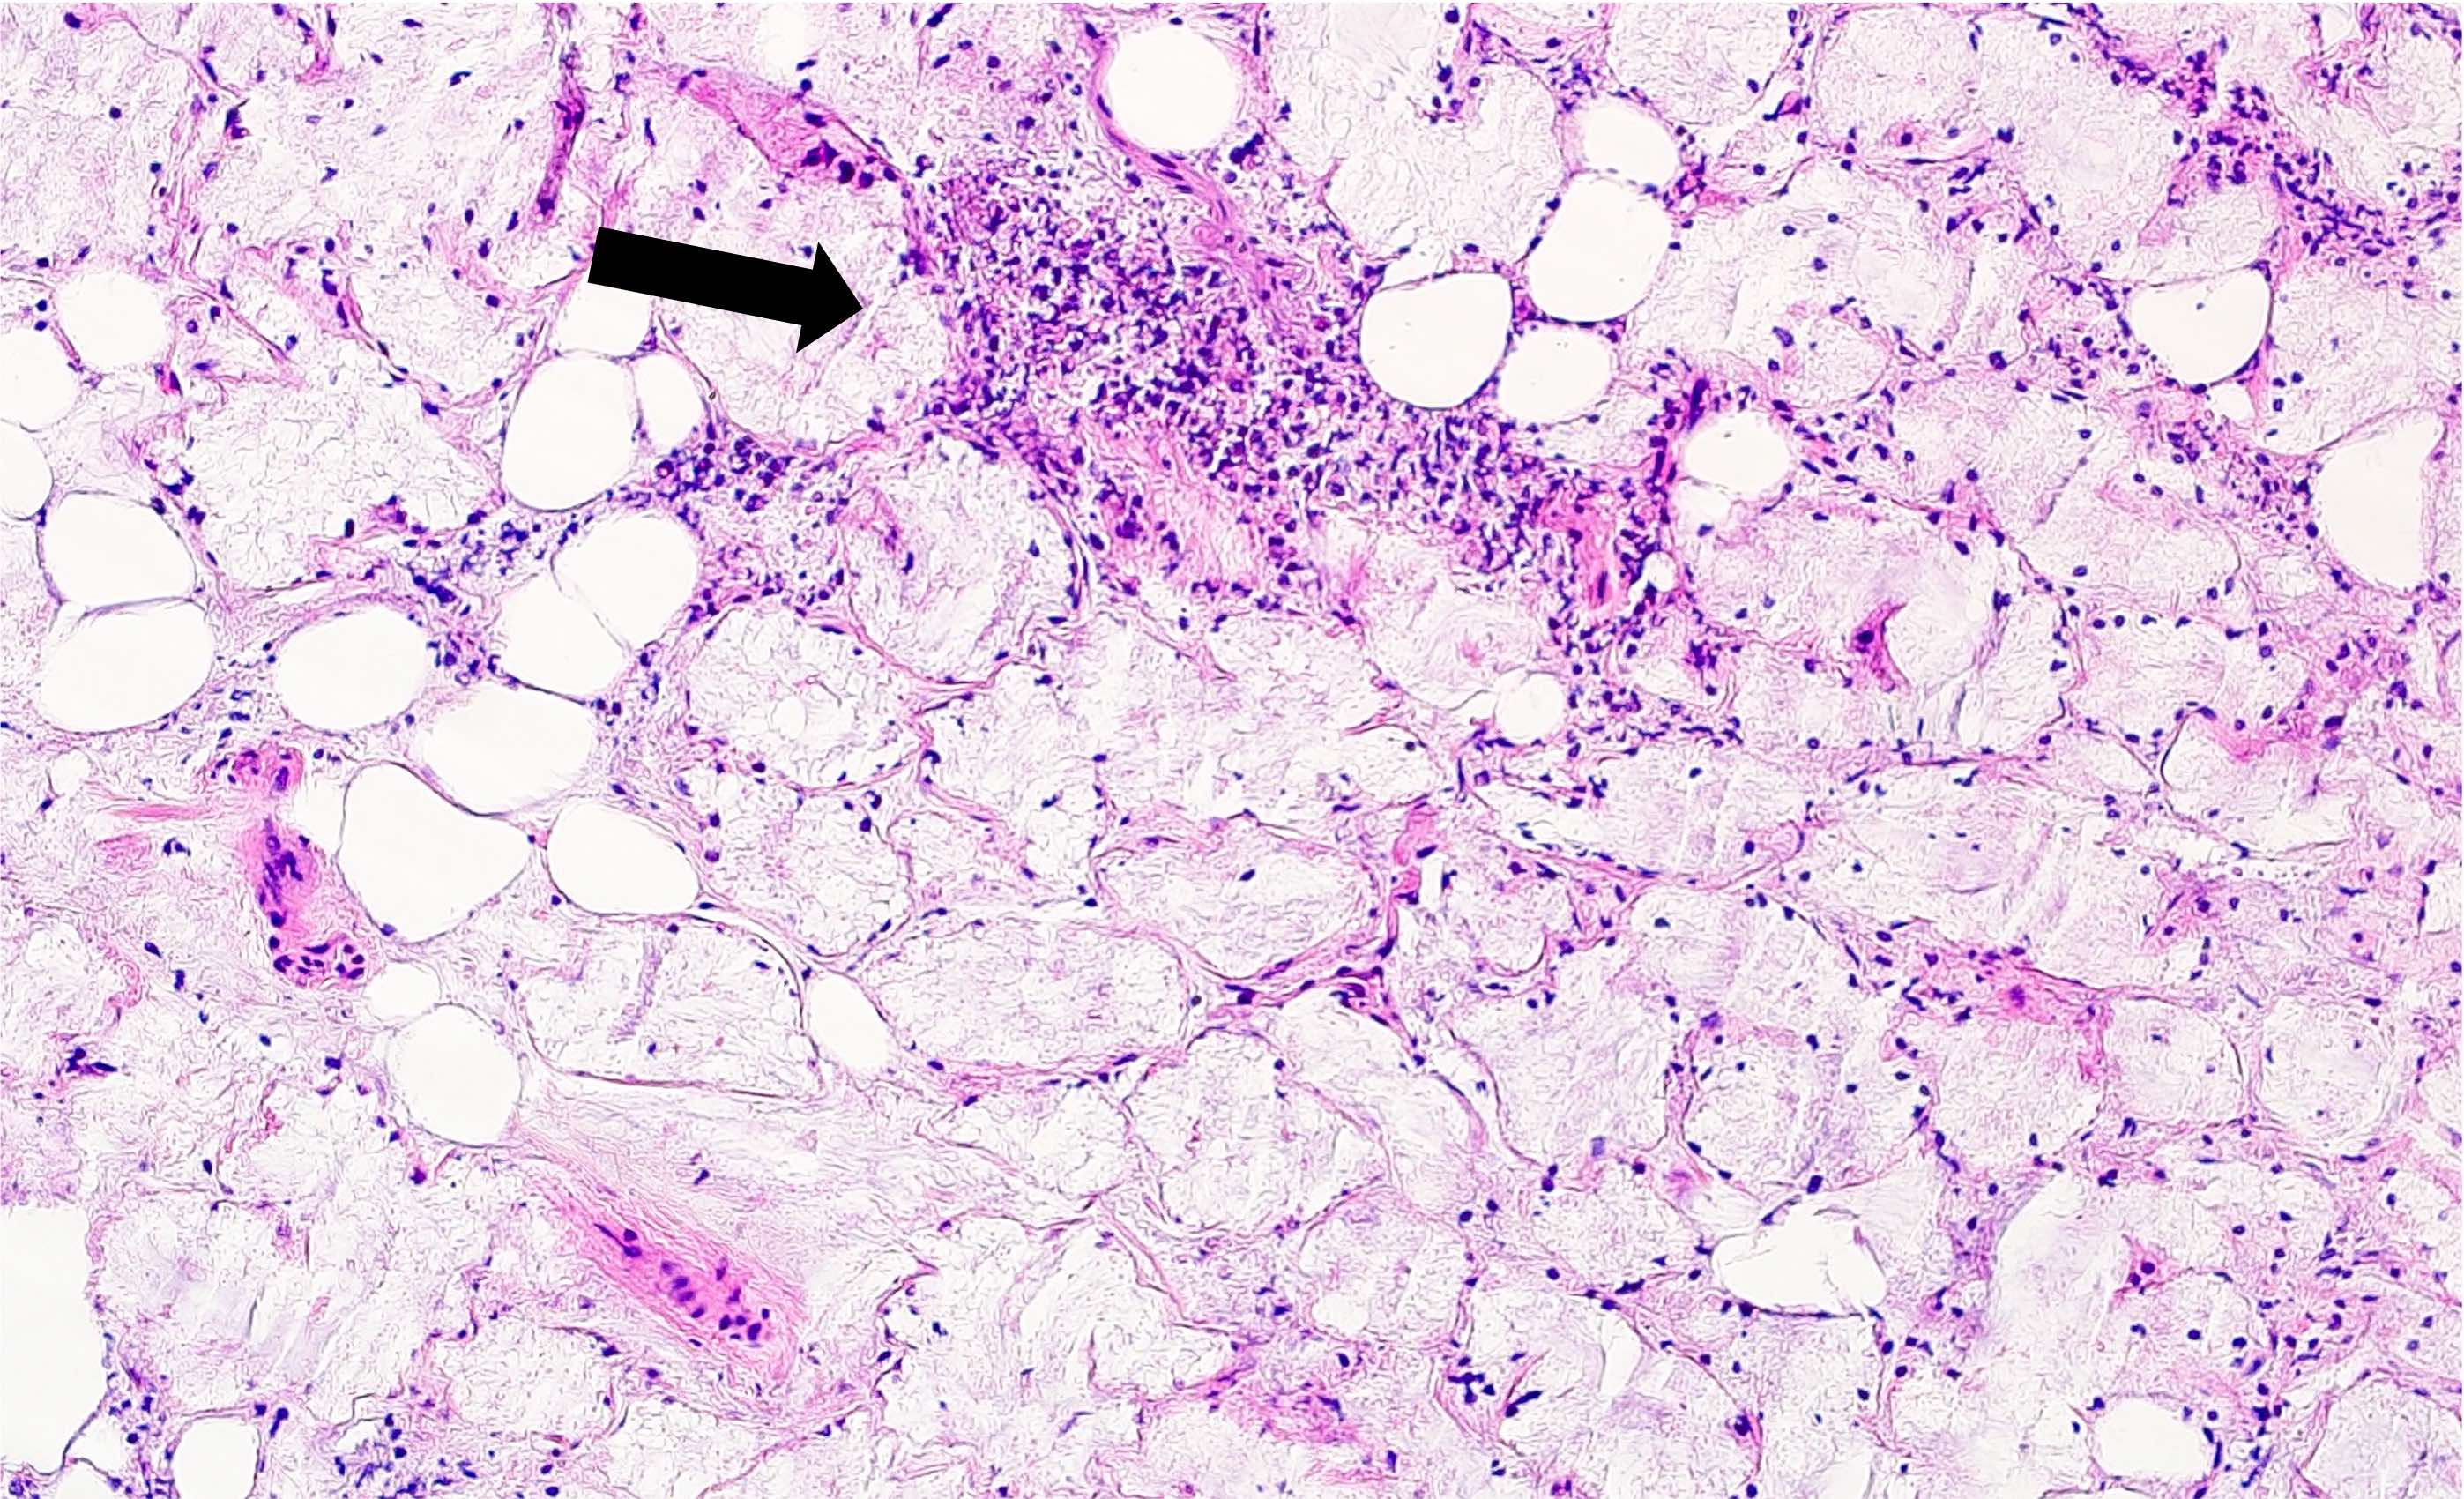

Microscopic (histologic) description

- Squamous metaplasia of ductal structures and acini with preservation of the salivary lobular architecture is an essential feature, according to World Health Organization (see WHO classification-oral cavity & oropharynx)

- Necrosis / infarction of acini characterized by loss of nuclei and cell borders with or without zones of spilled mucin

- Pseudoepitheliomatous hyperplasia with generally bland cytology or keratinocytic regenerative atypia

- Reactive, myxocollagenous background stroma

- Surface ulceration, granulation tissue and subacute inflammation may be present

- Has been conceptualized by 5 histologic stages of development and evolution: infarction, sequestration, ulceration, repair and healing (Int J Oral Surg 1982;11:283)

Microscopic (histologic) images